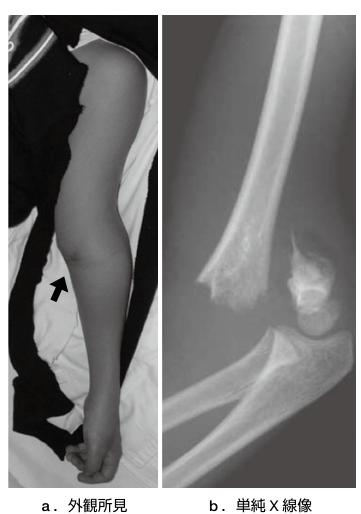

上腕骨顆上骨折は小児の肘関節周囲骨折の中でもっとも高頻度に発生する骨折です。

好発年齢は5〜7歳で,男女差は近年少なくなってきています。

右利きが多い点から,左側受傷が右側の約2倍とされています。

遊具(ジャングルジムや鉄棒など)から転落した際に受傷する発生機序がよく知られており,肘を完全に伸ばした状態で手先をついて転倒・転落することによって引き起こされる伸展型が97〜99%を占めると言われています。

診察を行い、神経血管損傷の有無やコンパートメント症候群の有無を確認します。

またレントゲンを撮像することで診断します。

ずれが少ないものはギプスによる保存治療を行います。4週程度ギプス固定を行うことが多いです。ずれの大きいものは手術となります。

その場合は総合病院へ紹介いたします。